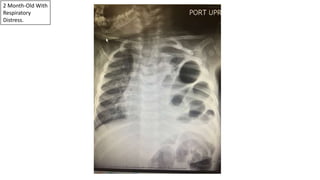

2 Month-Old With

Respiratory

Distress.

Diaphragmatic Hernia

Bowel In

The Chest